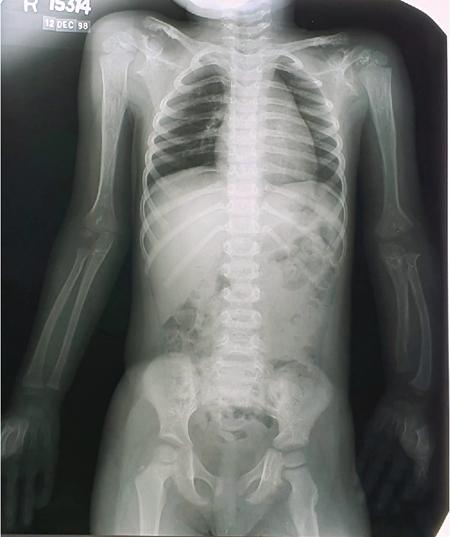

MISCELLANEOUS PAEDIATRIC RADIOGRAPHY – TECHNIQUES AND INTERPRETATION: SKELETAL SURVEY Padma V. Badhe The skeletal survey, generally performed in children, is a set of radiographs done in order to evaluate the entire skeleton. A skeletal survey, commonly used to evaluate skeletal dysplasias, acquired metabolic disorders and suspected child abuse, is still the key radiological investigation for the same. Hence, an explicit understanding of the technique along with the common disorders forms the basis of making a diagnosis in these paediatric pathologies. A skeletal survey is done for various skeletal dysplasias, non-accidental injury (battered baby syndrome) and suspected child abuse. It can also be done in cases of metabolic bone diseases, disseminated infections, multiple myeloma, eosinophilic granuloma. It is also used in evaluation of metastatic bone diseases and polyarticular arthropathy. Orthogonal views of the skull, spine, pelvis and one extremity are taken, preferable in standing position. For preterm babies/newborns, AP and lateral views of babygram may be taken. Projections: For skeletal dysplasias: Additional views: Both extremities may be taken if epiphyseal abnormalities and limb asymmetry is present. Focused views for specific pathologies may be taken. When a diagnosis remains uncertain, 1 year follow up is usually recommended. For preterm babies/newborns: AP and lateral views of babygram may be taken with additional specific views for extremities. For suspected non-accidental injury (NAI): AP and oblique view of chest is taken for better evaluation of the ribs. AP view of abdomen with pelvis. Both upper and lower limbs are evaluated. In lower limbs, two projections in AP and lateral (one with both femur including hip and knee joints; and another for foot and ankle) is taken. AP and lateral views of whole spine, skull. Oblique view of hands. A babygram should be avoided in cases of NAI, as subtle fractures are easily missed. Proper legal documentation while taking the views is very important and ideally two health care professionals must be present. For metabolic disorders: entire skeletal survey is usually not required. Specific views of hands, knees and spine may be taken with additional views depending on the suspected pathology. Centring point: Varies according to the part being examined. Angulation, collimation and orientation: Varies according to the part being examined. Images must be well collimated to obtain lower radiation dose. Detector size: Varies according to the part being examined: 8″ × 10″, 10″ × 12″, 11″ × 14″. Exposure: Ideally high kVp images are taken to reduce radiation dose. But in suspected NAI, low kVp/high mA images are recommended to better demonstrate findings. SID (Source Image Distance):100 cm Grid: Grids are not routinely used to image spine, pelvis, skull and abdomen in children. Radiation dosage: 0.3–3 mSv Essential image characteristics: Adequate spatial resolution, high signal to noise ratio, low kVp (50–70) for high contrast should be done. Excellent bone and soft tissue details are required. The presentation of skeletal dysplasia can range anywhere from minimal stunting of growth and bowing of limbs to severe dwarfism and multiple fractures. Knowledge of the commonly encountered dysplasias with an approach to arrive at a diagnosis is vital in any Radiologist’s practice The following flow chart summarizes the classification of important skeletal dysplasia: The following table summarizes the various dysplasias affecting the axial skeleton: TABLE 7.5.1.1 The following flow chart summarizes the working approach to skeletal dysplasias: Osteopetrosis (Albers-Schonberg disease/Marble bone disease) (Fig 7.5.1.1): Osteopetrosis clinically presents with anaemia/thrombocytopenia or cranial nerve compression. Radiological features include generalized increase in bone density with loss of medullary space. However, cortico-medullary appreciation with cortical thinning is also rarely seen. Bone within bone appearance with Erlenmeyer flask deformity is also noted. Pyknodysostosis (Figs. 7.5.1.2 and 7.5.1.3): patient presents with short stature. Unlike osteopetrosis, there is no anaemia. Radiographs show generalized increase in bone density with preserved medullary canal. There is mandibular hypoplasia with obtuse angle. Acro-osteolysis is also a feature. Dental caries with osteomyelitis of the jaw may be seen. Sclerosing dysplasia presenting as wavy undulating new bone formation. Usually monomelic, lower limb and along one side. The classic appearance is described as Dripping candle Wax sign. It is a Sclerosing dysplasia with radiological features of symmetric juxta-articular involvement in epimetaphyseal region. They are 1–10 mm in diameter and uniform in size. No metabolic activity is seen on bone scans. This skeletal dysplasia shows diffuse decrease in bone density with paper-thin cortex. Fractures heal in normal time but shows callus with poorly cellular matrix. Wormian bones and enlarged sinuses may be seen. Codfish vertebra (Biconcave vertebra) may be seen. Metaphyseal corner fractures are not seen in osteogenesis imperfecta that helps to differentiate it from battered baby syndrome. There are four types of OI out of which type one is most common (Figs. 7.5.1.6 and 7.5.1.7). The radiological features of MPS include Osteopenia and Universal platyspondyly. The intervertebral disc spaces are maintained. Proximal pointed metacarpals is an important radiological finding. Hurler’s syndrome show anteroinferior beaking with short and wide metacarpals. Varus deformity of humerus is characteristically seen in Hurler’s syndrome (Fig. 7.5.1.8). Mental retardation & corneal clouding is seen in Hurler’s syndrome whereas these Hunter’s disease has normal intelligence with no corneal clouding. Morquio’s syndrome shows central beaking (Fig 7.5.1.9). This skeletal dysplasia shows normal bone density with rhizomelic limb shortening and normal trunk. Narrowing of spinal canal is classically seen with decrease in the Interpedicular distance caudally. Other radiological features include trident hand (separation of middle & third fingers), Champagne glass pelvis (short, flat ilia and small sciatic notch), bullet nose vertebra and overexpansion of skull with narrow foramen magnum (Fig. 7.5.1.10). This skeletal dysplasia is characterized by normal bone density with dwarfism and normal craniofacial skeleton. The interpedicular distance is normal. There is severe platyspondyly with anterior tonguing (disappears at older age). Other radiological features include increased disc space, short stubby metacarpals, small irregular epiphysis and widened metaphysis. Anterior tonguing is a feature of Pseudoachondroplasia. This form of skeletal dysplasia involves the spine and epiphyses (Fig. 7.5.1.11). There is normal bone density with rhizomelia. Spine and Pelvis can be involved. Premature osteoarthritis can be seen. The other characteristic features include Platyspondyly and small irregular epiphysis. There are two forms Spondyloepiphyseal dysplasia Congenital and Spondyloepiphyseal dysplasia Tarda. Spondyloepiphyseal dysplasia Congenita is Autosomal dominant and shows pear-shaped vertebrae. Spondyloepiphyseal dysplasia Tarda is X Linked recessive with heaped up vertebrae. It has two forms. The first form is Conradi Hunermann syndrome which is autosomal dominant characterized by asymmetric limb shortening with metaphyseal flaring (Fig. 7.5.1.12). The Autosomal recessive form is Fatal in first few years. Rickets: Rickets refers to deficient mineralization of the growth plate in the paediatric population due to deficiency of vitamin D. In an immature skeleton, there is abnormal mineralization at the zone of provisional calcification in the metaphysis due to osteoid deposition resulting in widening of the growth plate. The features of rickets include fraying, splaying and cupping (Fig. 7.5.1.13). Fraying denotes indistinct margins of the metaphysis whereas splaying denotes widening of metaphyseal ends. Term ‘Cupping’ is used for increased concavity of the metaphysis. These findings are typically seen involving areas of active growth (e.g. distal femur and proximal tibia in the knee) Bowing is a result of associated osteomalacia leading to weakening of weight-bearing lower limb bones. Other bone deformities such as genu valga, genu varum, protrusio acetabuli can also be seen. The lower ribs may also be drawn inwards inferiorly by the attachment of the diaphragm this is called Harrison’s sulcus. Scurvy: Scurvy is a result of dietary deficiency of Vitamin C (ascorbic acid). The classic presentation is that of a patient with an increased bleeding tendency and osteopenia with poor wound healing. Features of scurvy include generalized osteopenia with cortical thinning termed as ‘pencil-point’ cortex. Other radiological findings include the periosteal reaction due to subperiosteal haemorrhage. Expansion of the costochondral junctions occurs forming scorbutic rosary. Bleeding into the joint spaces may result in hemarthrosis. Circular, opaque radiologic shadow surrounding epiphyseal centres of ossification may result from bleeding (Wimberger ring sign) (Fig. 7.5.1.14). Frankel line may be seen. It represents dense zone of provisional calcification. Lucent metaphyseal band is seen underlying Frankel line called as Trümmerfeld zone. Metaphyseal spurs may be seen that result in cupping of the metaphysis (Pelkin spur). Pelkin fracture (metaphyseal corner fracture) can also be seen. Images obtained must be of good resolution with adequate bone and soft tissue details. Additional views: They have already been described in positioning. CT Brain in can be done in cases of NAI to look for subdural hematomas. A skeletal survey is the first-line imaging modality for evaluation of skeletal dysplasia, nonaccidental injury and metabolic bone diseases. The skeletal survey must be tailored according to the respective indication. It helps to characterize syndromic patterns in skeletal dysplasias, with evaluation of complications. In cases of diagnostic dilemmas, additional focused view and occasionally yearly follow-up is recommended. A high index of suspicion is needed in utilizing skeletal survey as a diagnostic modality in NAI. At the same time, one must also remember the legal and social implications of making this diagnosis. BABYGRAM Babygram is a colloquial term used for a radiograph of the whole body of a newborn or just the chest and abdomen (thoracoabdominal babygram) on a single image. As the name suggests it is a rather non-targeted study. It is most commonly requested after line placement. Evaluation of skeletal abnormalities in a deceased foetus is typically performed using anteroposterior and lateral views of a babygram. It helps in pointing out skeletal causes of death in stillborn or dead foetuses. This will help the treating physician and parents understand the reason for baby’s death. This will also help in future genetic counselling of the couple. Sometimes chest or abdominal radiographs of the baby are requested but due to radiographers error or inexperience with small babies, there is inclusion of the region not to be assessed leading to a false babygram. Babygram is most frequently done after line placement in neonates, to view the position of the umbilical vein or artery catheter and to confirm appropriate placement. It is a useful modality in skeletal dysplasias (Fig. 7.5.1.15) like osteogenesis imperfecta, thanatophoric dysplasia and chondrodysplasia punctata. It can also be used for skeletal deformations probably caused by foetus akinesia and in cases of Caudal regression syndrome. In stillborn foetuses, it is used for evaluation of skeletal dysplasias prior to an autopsy (Fig. 7.5.1.16). It is also used in screening for surfactant deficiency and in cases of Necrotizing Enterocolitis in preterm babies where it can help to see the bowel dilatation, intramural and portal venous gas. It can be done in aneuploidies like trisomy 18 and in cases of sudden infantile death syndrome. All the essential equipment and room need to be prepared including the exposure factor. This should be done prior to placing the baby on the table to prevent any neonatal heat loss. Ensure that the baby is correctly identified. Give brief explanation to the patient’s parents regarding the procedure, its risks and benefits. Ensure that the accompanying relative is not pregnant (if female). Parents/guardians/nurses should be instructed to hold the baby with arms above the head and legs straight down. Sandbags/tapes can be used to immobilize the baby. Avoid taking the radiograph when baby is crying. Normal appearance: The endotracheal tube should lie in the lower third of trachea, distance can vary with position of baby’s head. Umbilical artery catheter has an inferior dip along the internal iliac artery, which then turns superiorly along the aorta. The tip should lie in the mid-thoracic aorta (T6–T10) or lower (L3–L4) away from aortic branches to prevent any thrombosis. Umbilical venous catheter does not have the inferior curvature, but rather a posterolateral angulation to the right near the liver through the ductus venosus. The tip should lie in the superior IVC or right atrium at T8/T9 vertebral level (Fig. 7.5.1.17). Portal venous gas may be seen initially after insertion. In a stillborn foetus, the approximate gestation age of the foetus and corresponding ossification centres must be known. In early gestation, the lack of appearance of an ossification centre may be mistaken for skeletal dysplasia. Both chest and abdomen should be included. In a rotated patient, the distance between the spinous process to medial end of clavicles will be asymmetric. The medial end of clavicle should overlap the lung apex, if above, suggests lordotic image. Motion artefacts to be reduced as much as possible. A crying neonate may result in an expiratory film, and hence must be evaluated accordingly. In evaluation of skeletal dysplasias in the newborn, additional views of skull and hand have to be obtained. Baby gram is a useful diagnostic investigation for position of the paediatric umbilical catheters. It helps in general survey in skeletal dysplasia (Fig. 7.5.1.18). It is a simple, effective study in deceased foetus for diagnosis and further counselling, sometimes obviating the need for an autopsy. As baby gram is a non-targeted study, it increases the dose of radiation for the baby. As the exposure settings remain same for the entire body of the baby, the quality of the image decreases. This increases the chances of missing subtle findings. The babygram in a neonate is currently used to localize umbilical catheters. In stillborn fetuses, it is still an important study for documenting and confirming skeletal dysplasias. Understanding the normal appearance as per gestation age and patterns of various common skeletal dysplasias is essential for evaluation. Being a non-targeted study, it should not be used as an alternative study to evaluate the chest or abdomen considering radiation exposure and poorer image quality. INVERTOGRAM Invertogram was first described by Wangensteen and Rice in 1930. It was used as a first investigation to be ordered in evaluation of infants with clinically diagnosed or suspected Anorectal Malformation (ARM). ARM is a serious but surgically treatable congenital malformation with approximate incidence of 1 in 5000 live births. Though the diagnosis of this condition is based on clinical history and physical examination, imaging plays an important role in deciding the type of ARM, and associated complications to aid in management. International classification of anorectal malformations is as follows. Syndromic association is seen as a part of VACTERL defects, trisomy 21 13 and 18, Klippel Feil syndrome, cat eye syndrome etc. The main indication of Invertogram is to evaluate anorectal malformation in a neonate. A radio-opaque marker is placed over the external anal opening. Infant is held inverted by holding both thighs, maintaining this posture for at least 5 minutes before taking an X-ray in true lateral position (Fig. 7.5.1.19). Exposure is made during inspiration. The Invertogram should ideally be done 24 hours after birth as, the rectal gas may not reach the terminal segment if study is done too early. Pubo-coccygeal line (PCL) is drawn from upper border of pubic symphysis (which corresponds to centre of pubic bone on lateral X-ray) to sacrococcygeal junction. I point is the inferior most point of ischial ossification centre. A line which is drawn parallel to PC line passing through the I point is called I line. ‘A’ point is represented by marker placed at anal pit. The position of rectal pouch gas shadow is observed with respect to these lines and appropriate diagnosis is made (Fig. 7.5.1.21). A diagnosis of high ARM is made when gas shadow of rectal pouch is cranial to PCL. If rectal pouch gas shadow is in between PCL and I line, it is called as intermediate ARM and if it is caudal to I line, it is diagnosed as low ARM. Gas in urinary bladder or vagina or beaking of gas shadow of rectal pouch indicates fistula into one of these sites. Associated congenital abnormalities like spinal defects are also looked for in the invertogram (Fig. 7.5.1.22). Invertogram done too early (less than 24 hours) may not demonstrate rectal gas. Meconium plugging the terminal segment gives false position of the rectal gas. Positioning can cause discomfort to child and an irritated crying child actively contracts the sphincter muscles, pushing the gas shadow higher. Rectum may be pulled cephalad due to gravity in inverted position. The rectal gas may escape through an associated fistula. Erroneous interpretation can also occur due to sacral anomalies and when gas in vaginal cavity is misinterpreted as distal rectal gas. Both ischial bones should superimpose and terminal blind loop should be well distended. It is an easily available modality and can be done quickly, does not require additional equipment. It has lesser radiation dose as compared to CT invertogram. It provides a rough guide as to the type of ARM and decides management. Higher localization of obstruction due to various causes like meconium plugging, imaging done too early etc. as described above in pitfalls. It is more uncomfortable to the baby as compared to the prone cross-table lateral view, and a crying baby contracts the puborectalis leading to erroneous results. K. L. Narasimharao et al. modified the technique and proposed cross-table lateral view for evaluation of infants with ARM’s which has shown equal or better information and has now replaced invertogram (Fig. 7.5.1.23). Prone cross-table lateral view is considered equivalent or even better in determining the level of anomaly. Positioning is in this view is prone in genupectoral position (at least for 3 minutes). It is taken in true lateral and during inspiration. The lines used to delineate types of ARM is essentially the same as in an invertogram. It is preferred over invertogram as relatively easy positioning of the infant and less discomfort allows for better cooperation of neonate during the study. It also eliminates the effect of gravity. ARM with fistula is better delineated as, in an invertogram, fistula/gas is at the highest level and gas may escape through it. CT invertogram is another modality that delineates anatomy better but is rarely used. In the era of cross-section imaging, MRI and USG have opened new modalities for accurate diagnosis of ARM, but invertogram being readily available, inexpensive, quick and cost-effective is used as first investigation for evaluating a patient with suspected or confirmed case of ARM. Cross-table lateral view has replaced invertograms as it is more patient-friendly and equally effective. UPPER GASTROINTESTINAL SERIES Rushit S. Shah An upper gastrointestinal (GI) study is a radiographic examination of the GI tract from the pharynx to the ligament of Treitz after oral administration of contrast agent. The use of upper GI studies is gradually declining with the increasing availability of paediatric endoscopy and the challenge for the modern radiologist to work in conjunction with the surgeon and gastroenterologist to select the right patients for an upper GI series. However, the upper GI series remains the key for demonstrating many anatomical abnormalities. The upper GI series is also useful in evaluating gastro-oesophageal reflux in conjunction with 24 pH monitoring. The upper GI examination is useful in evaluating many conditions including but not limited to: